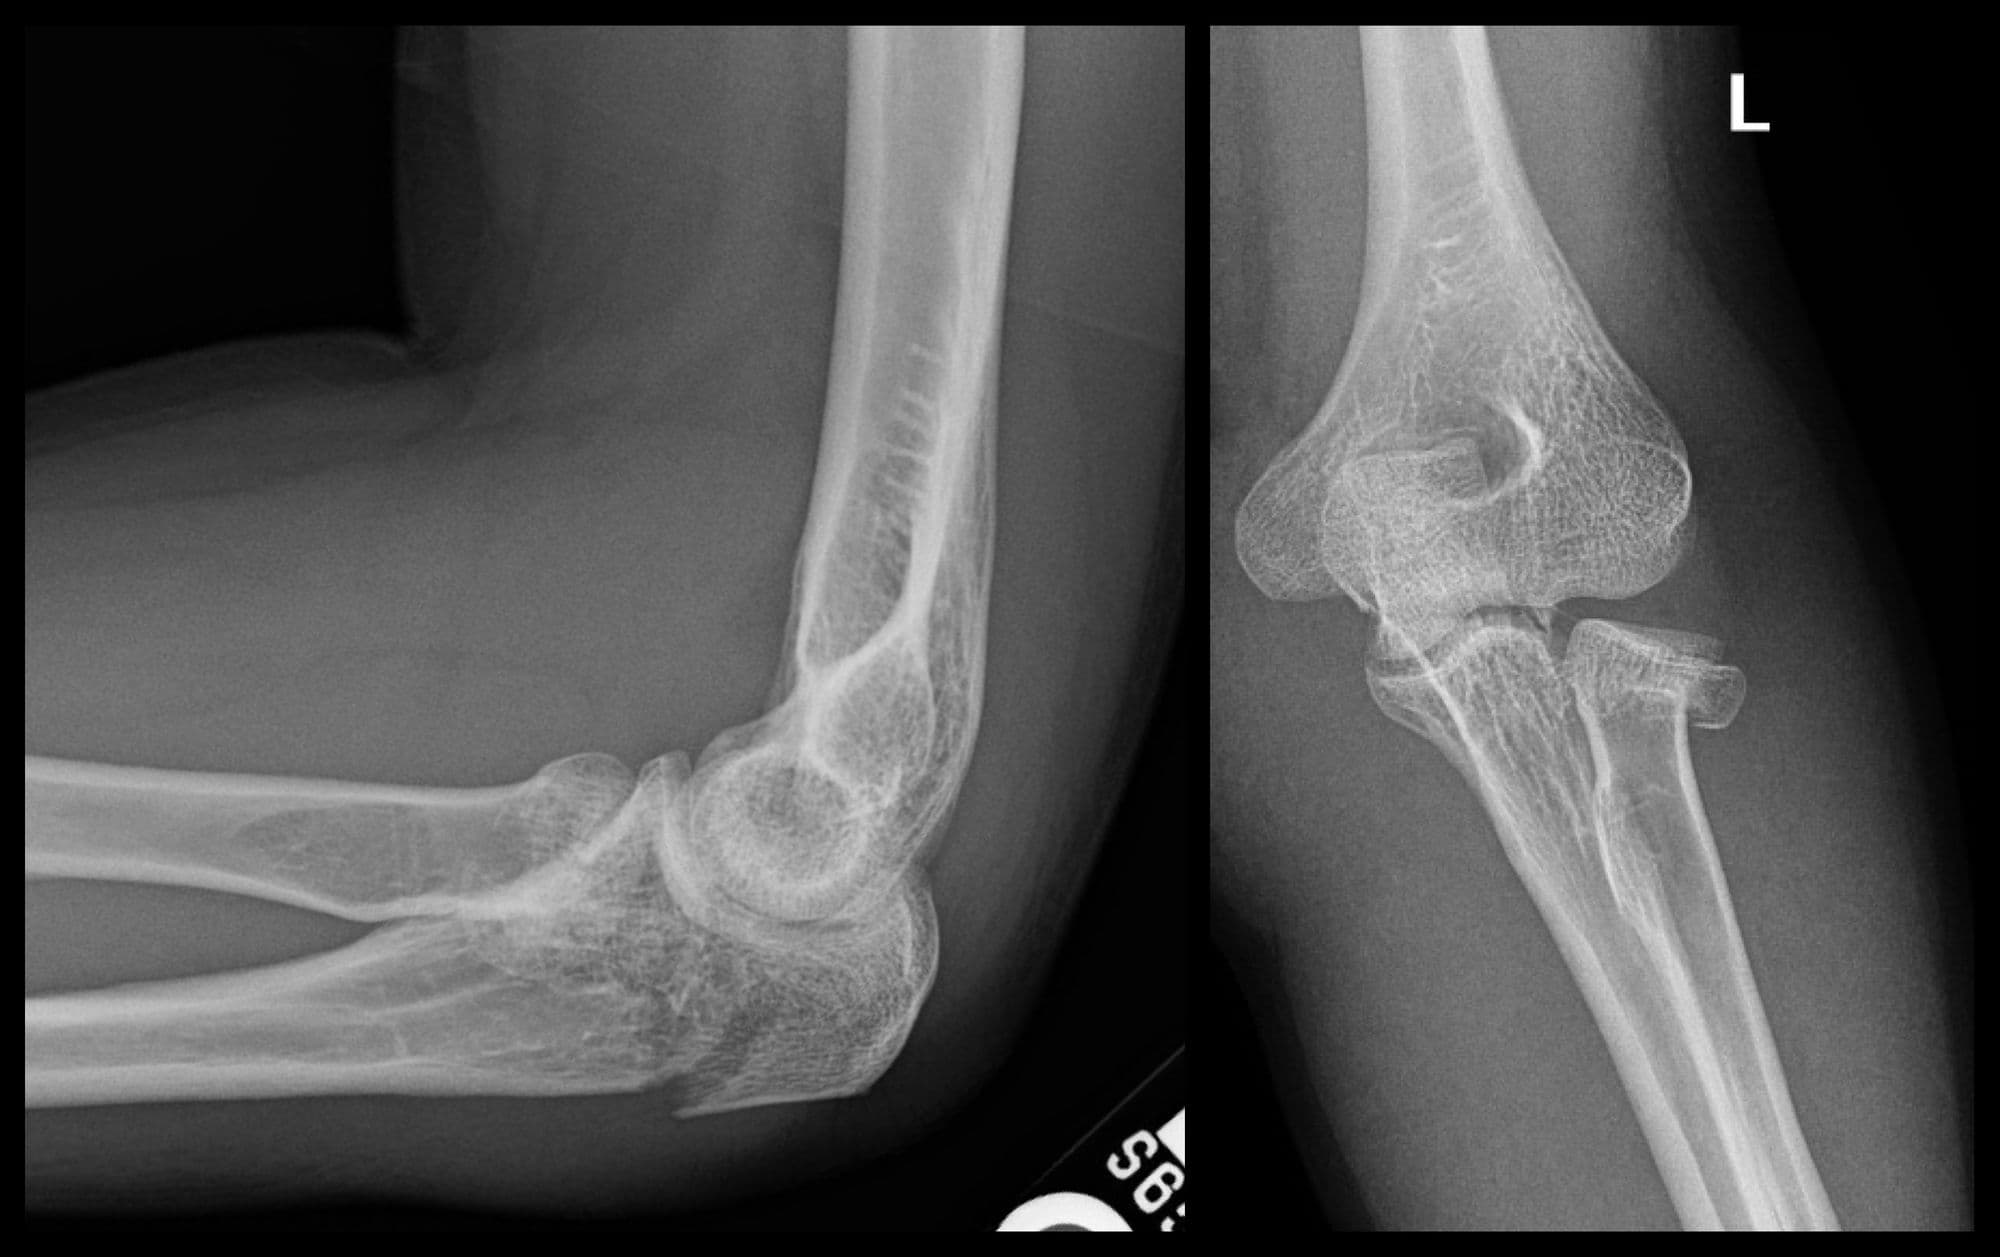

Segmental Humerus ORIF

Imaging

Pre-op